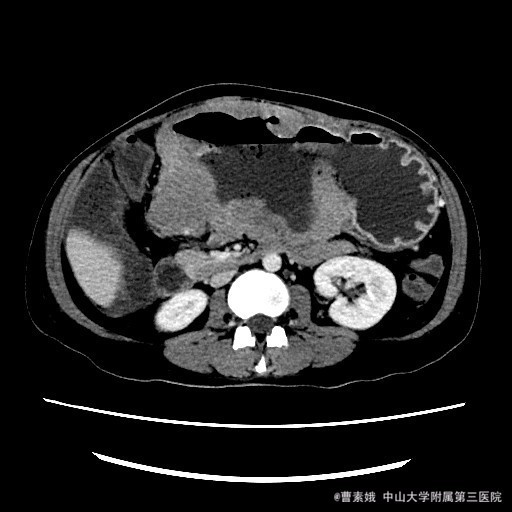

患者:女 37岁 主诉:发现腹部包块伴恶性、呕吐1月余 病史:患者平素一直有胃部不适,偶有胃痛、饱胀感不适,一直口服药物治疗,未见明显好转,1月前自觉腹部包块,并出现恶性、呕吐。呕吐为胃内容物。

查体:左上腹触及一包块,较柔软,余未特殊。 辅助检查:全腹CT平扫+增强示:胃体至胃窦部胃壁弥漫性增厚并软组织肿块,考虑淋巴瘤可能性大。

入院诊断:胃淋巴瘤(?) 治疗:诊断:胃淋巴瘤(?) 治疗:入院后(胃部肿物)送检组织镜下见胃粘膜固有层及肌层结构破坏,并见中等偏大异形淋巴样细胞弥漫浸润,局部成片分布,细胞具有异型性,可见核仁,核分裂象易见,结合免疫组化结果,符合高级别B细胞源性淋巴瘤,考虑滤泡淋巴瘤(FL3b)。组织少,肿瘤成份少,不完全排除弥漫大B细胞性淋巴瘤(生发中心亚型)。建议结合临床。排除手术禁忌症后,于腹腔镜下胃大部分切除术 。 术程顺利,患者恢复较好,建议其进一步化疗,患者表示拒绝后出院。